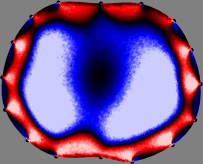

Figs. 3 and 4 compare the performance of the proposed FER method in (20) with the standard regularized least-squares method ((19) when is the identity matrix). The regularization parameter of the standard method was heuristically chosen for its best performance, and the parameter of the FER method was set to be one of three different values . The injection current was 1 mA at 100 kHz, and the frame rate was 9 frames per second. The reference frame at was obtained from the maximum expiration state. The measured data, , represent the voltage differences between each time and . The blue regions, which denote where conductivity decreased by inhaled air, increased during inspiration and decreased during expiration. The FER method with was clearly more robust than the standard method that produced more artifacts originated from the inversion process.

| Standard | |

||||||||||

| FER () | |